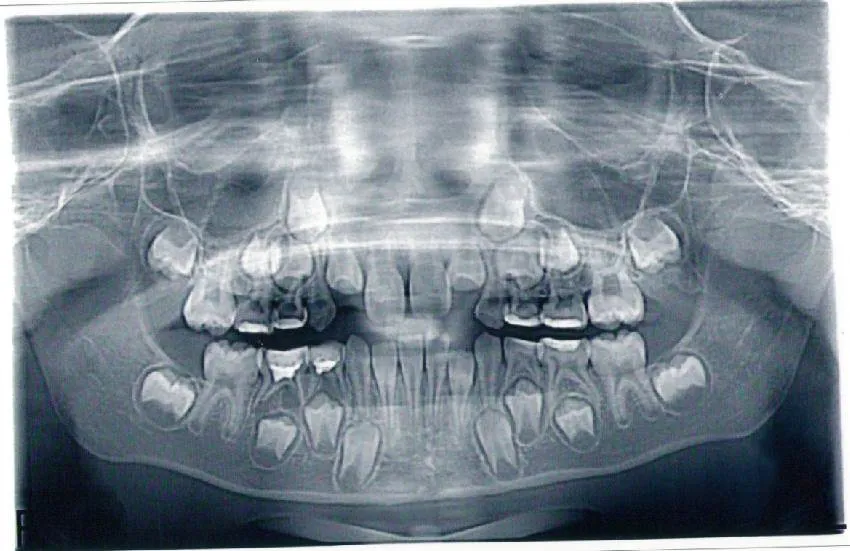

Перед началом ортодонтического лечения или во время активного прорезывания постоянных зубов выполняется панорамная ортопантомограмма. Этот вид визуализации позволяет взглянуть на все зачатки зубов на снимке, а также на молочные зубы, представляя полную картину зубного ряда и челюсти.

Для точного выявления клинической ситуации важно провести компьютерную томографию или сделать прицельный снимок, так как может оказаться, что за молочным зубом находится несколько зачатков постоянного зуба, что можно увидеть только на рентгенограмме.